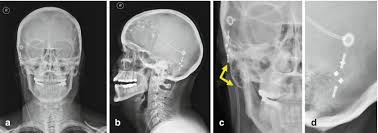

Plain X Ray Shunt Series Ap Anteroposterior A Ap Skull Xray That Download Scientific Diagram

Shunt Series Radiology Reference Article Radiopaedia Org

Radiologic Identification Of Vp Shunt Valves And Adjustment Pediatric Neurosurgery Leipzig

Ap and lateral abdomen ap and lateral chest ap and lateral c spine ap and lateral skull.

Vp shunt x ray positioning. The shunt series is a set of radiographic images performed to assess the location and integrity of a ventriculoperitoneal shunt. In the context of hydrocephalus there are a multitude of therapeutic options that can be explored in order to improve patient outcomes. The external portion of the catheter is connected to a valve that regulates the flow of csf based on a preset pressure.

Programmable csf shunt valves. Shunt series for vp shunt x ray guideline. Indications departmental protocols will vary but the overall goal is to image the shunt in its entirety to assess.